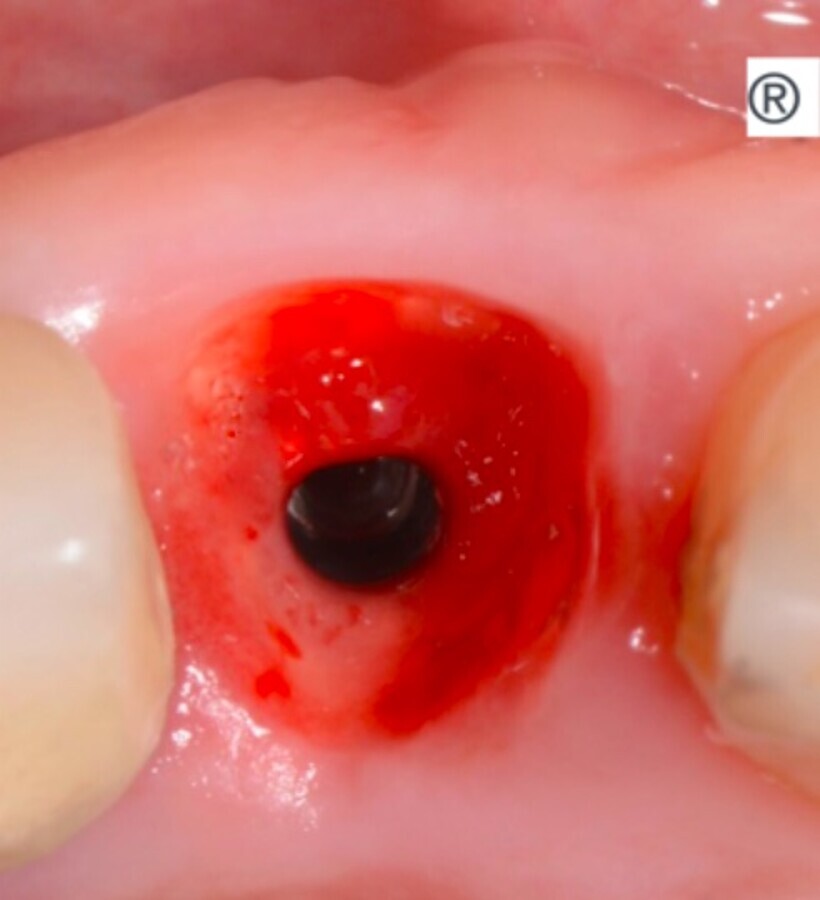

Imagen 4. Emergencias obtenidas con los dispositivos Esculgar.

Manejamos el espacio biológico desde el sistema de implantes, aprendimos a ver el hueso sin cortar, sin exponerlo, a colocar el implante en posición protética ideal.

La conjunción de conceptos quirúrgicos no invasivos, donde las incisiones son la última alternativa, la no reapertura y el sistema de implantes que no filtra ni sufre micromovimientos, el respeto del espacio biológico que se conforma en el momento de la cirugía, muy similar al que tienen los dientes naturales, nos entrega restauraciones sin reabsorción ósea periimplantar en más de un 90% de los casos.